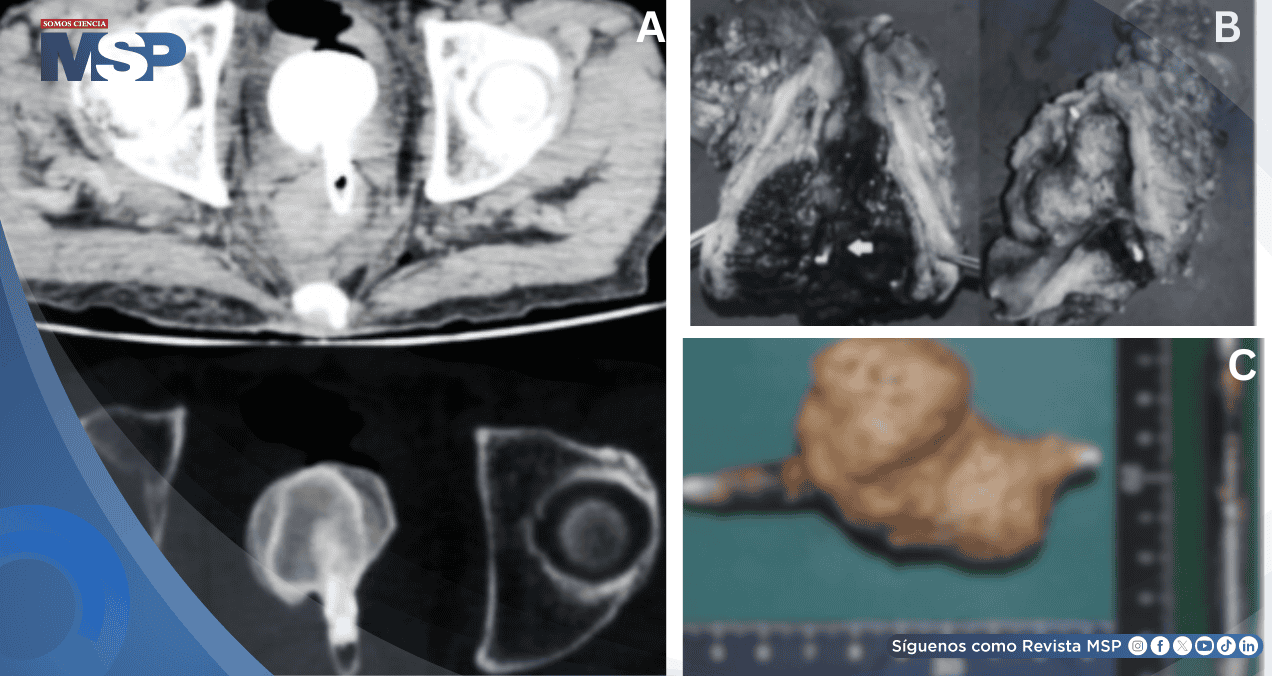

La autopsia reveló un cálculo vesical gigante de 6,5 cm adherido a un delineador de ojos que había penetrado desde el recto hacia la vejiga, causando pielonefritis y sepsis fatal.

Internamente se identificó un delineador de ojos de aluminio (9 × 0,8 cm) penetrando la pared rectal anterior hacia la vejiga, con un cálculo vesical gigante de 6,5 × 6,0 × 4,0 cm adherido. La mucosa rectal circundante estaba eritematosa y edematosa. El riñón izquierdo pesaba 250 g, estaba congestivo y rojizo, mientras el derecho pesaba 110 g y lucía pálido. Había hidronefrosis bilateral. El peritoneo permanecía intacto sin signos de perforación.